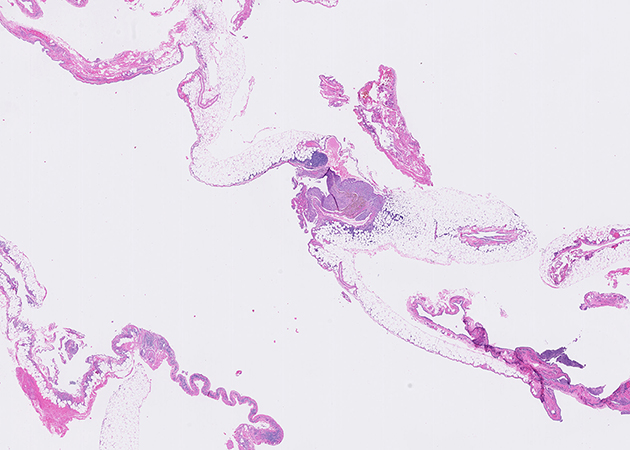

Representative H&E histological images of the pleurectomy specimen are shown in Figures 2 to 4 (1X and 20X magnification) and immunohistochemical stains for CD10 and estrogen receptor performed on the area of Figure 4 are presented in Figures 5 and 6, respectively. The diaphragmatic pedunculated polyp was composed of fibroadipose tissue with multifocal nodules with similar histological features as Figure 4 (not shown).